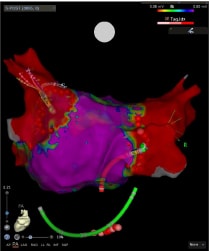

基本となる薬物療法に加えて、当院では高周波カテーテルアブレーションに力を入れています。当院のアブレーションは以下のような点で大きな進歩をしてまいりました。

- 心臓の形態や電位に関する情報をカテーテルを用いて把握

- コンタクトフォース(カテーテルによりかかる力)を可視化し適切な力で焼灼